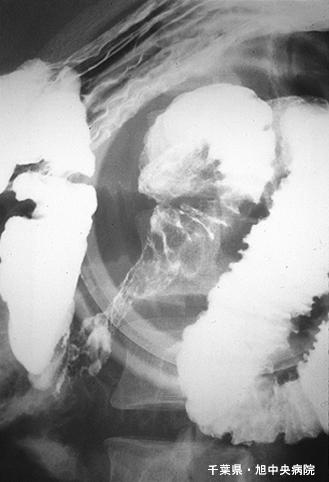

미만성의 조대한 점막면과 궤양을 동반한 소장 아밀로이드증(증례제시:치바현, 아사히중아병원)

염증성・궤양성 질환/소화관 유전분증

소장/2개 이상

X-P